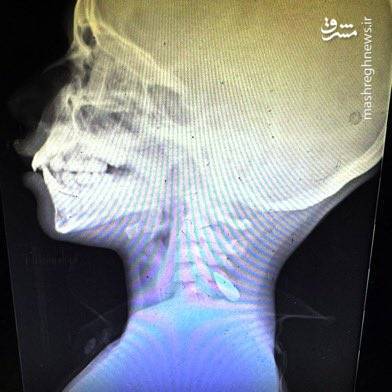

آنان با تصاویر رادیوگرافی از اعدام و شلیک به سر و گردن کودکان با (گلولههای ۵.۵۶ ناتو) مستندات آوردهاند و از کشتار، گرسنگی دادن و گورهای جمعی روایاتی هولناک کردهاند.